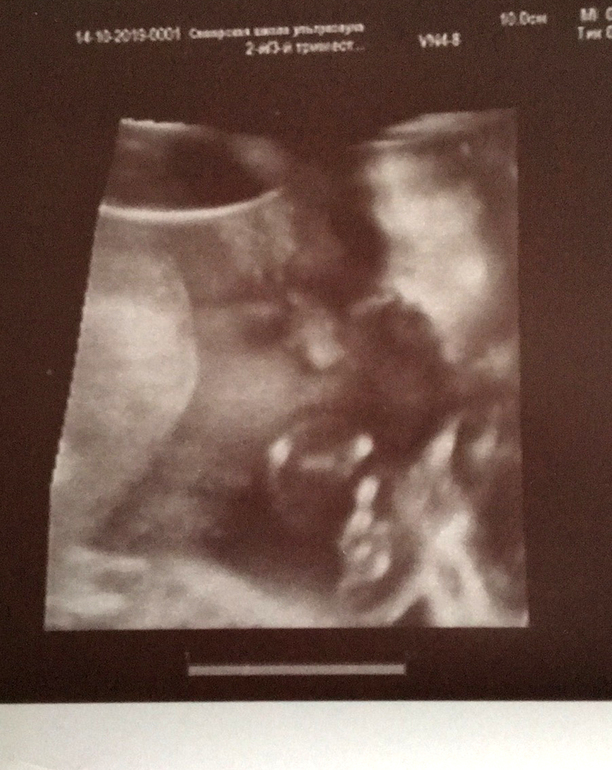

Фотогалерея (Наши пузики и детки)Сегодня была на промежуточном Узи♥️. Все хорошо,весим 900г. Опережаем на 1.5-2 недели с самого начала. Беременность протекает легко,как и первая в принципе,только детки отличаются полом и темпераментом. Еще живот растет быстрее и я расту быстрее,уже +8кг🤰🏼